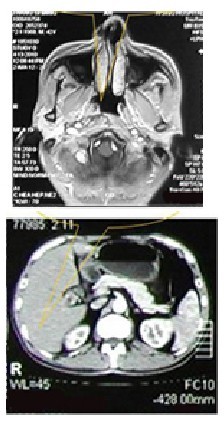

【康复路程】:鼻咽镜取病理检测及MRI核磁共振,诊断为鼻咽癌。2013年9月17日,进行WB-1无创全身热疗系统结合放疗。10月20日入院复查CT检查发现鼻咽部肿块缩小,3个月后再次复查,CT显示肿块完全消失,患者康复。至今仍坚持每年按时入院复查,健康状况良好。